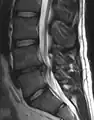

L'imagerie par résonance magnétique peut montrer la hernie, le canal vertébral, les nerfs, les tissus environnants. Les tissus mous sont les mieux analysés par cet examen qui est le plus performant pour le diagnostic de hernie discale. Les images pondérées en T2 montrent clairement la hernie.

IRM lombosacrée sagittale montrant une hernie discale de niveau L4-L5.

IRM lombaire sagittale montrant une hernie discale de niveau L4-L5.

IRM lombaire sagittale montrant des protrusions discales.